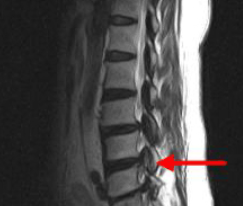

척추협착증 진단, CT와 MRI 촬영 등을 통해서 척추관 크기와 주변 관절과 인대, 추간판의 상태를 알아보고 종합적으로 진단을 하게 됩니다. 근전도 검사와 신경전도 검사도 함께 병행해서 하게 되겠습니다.